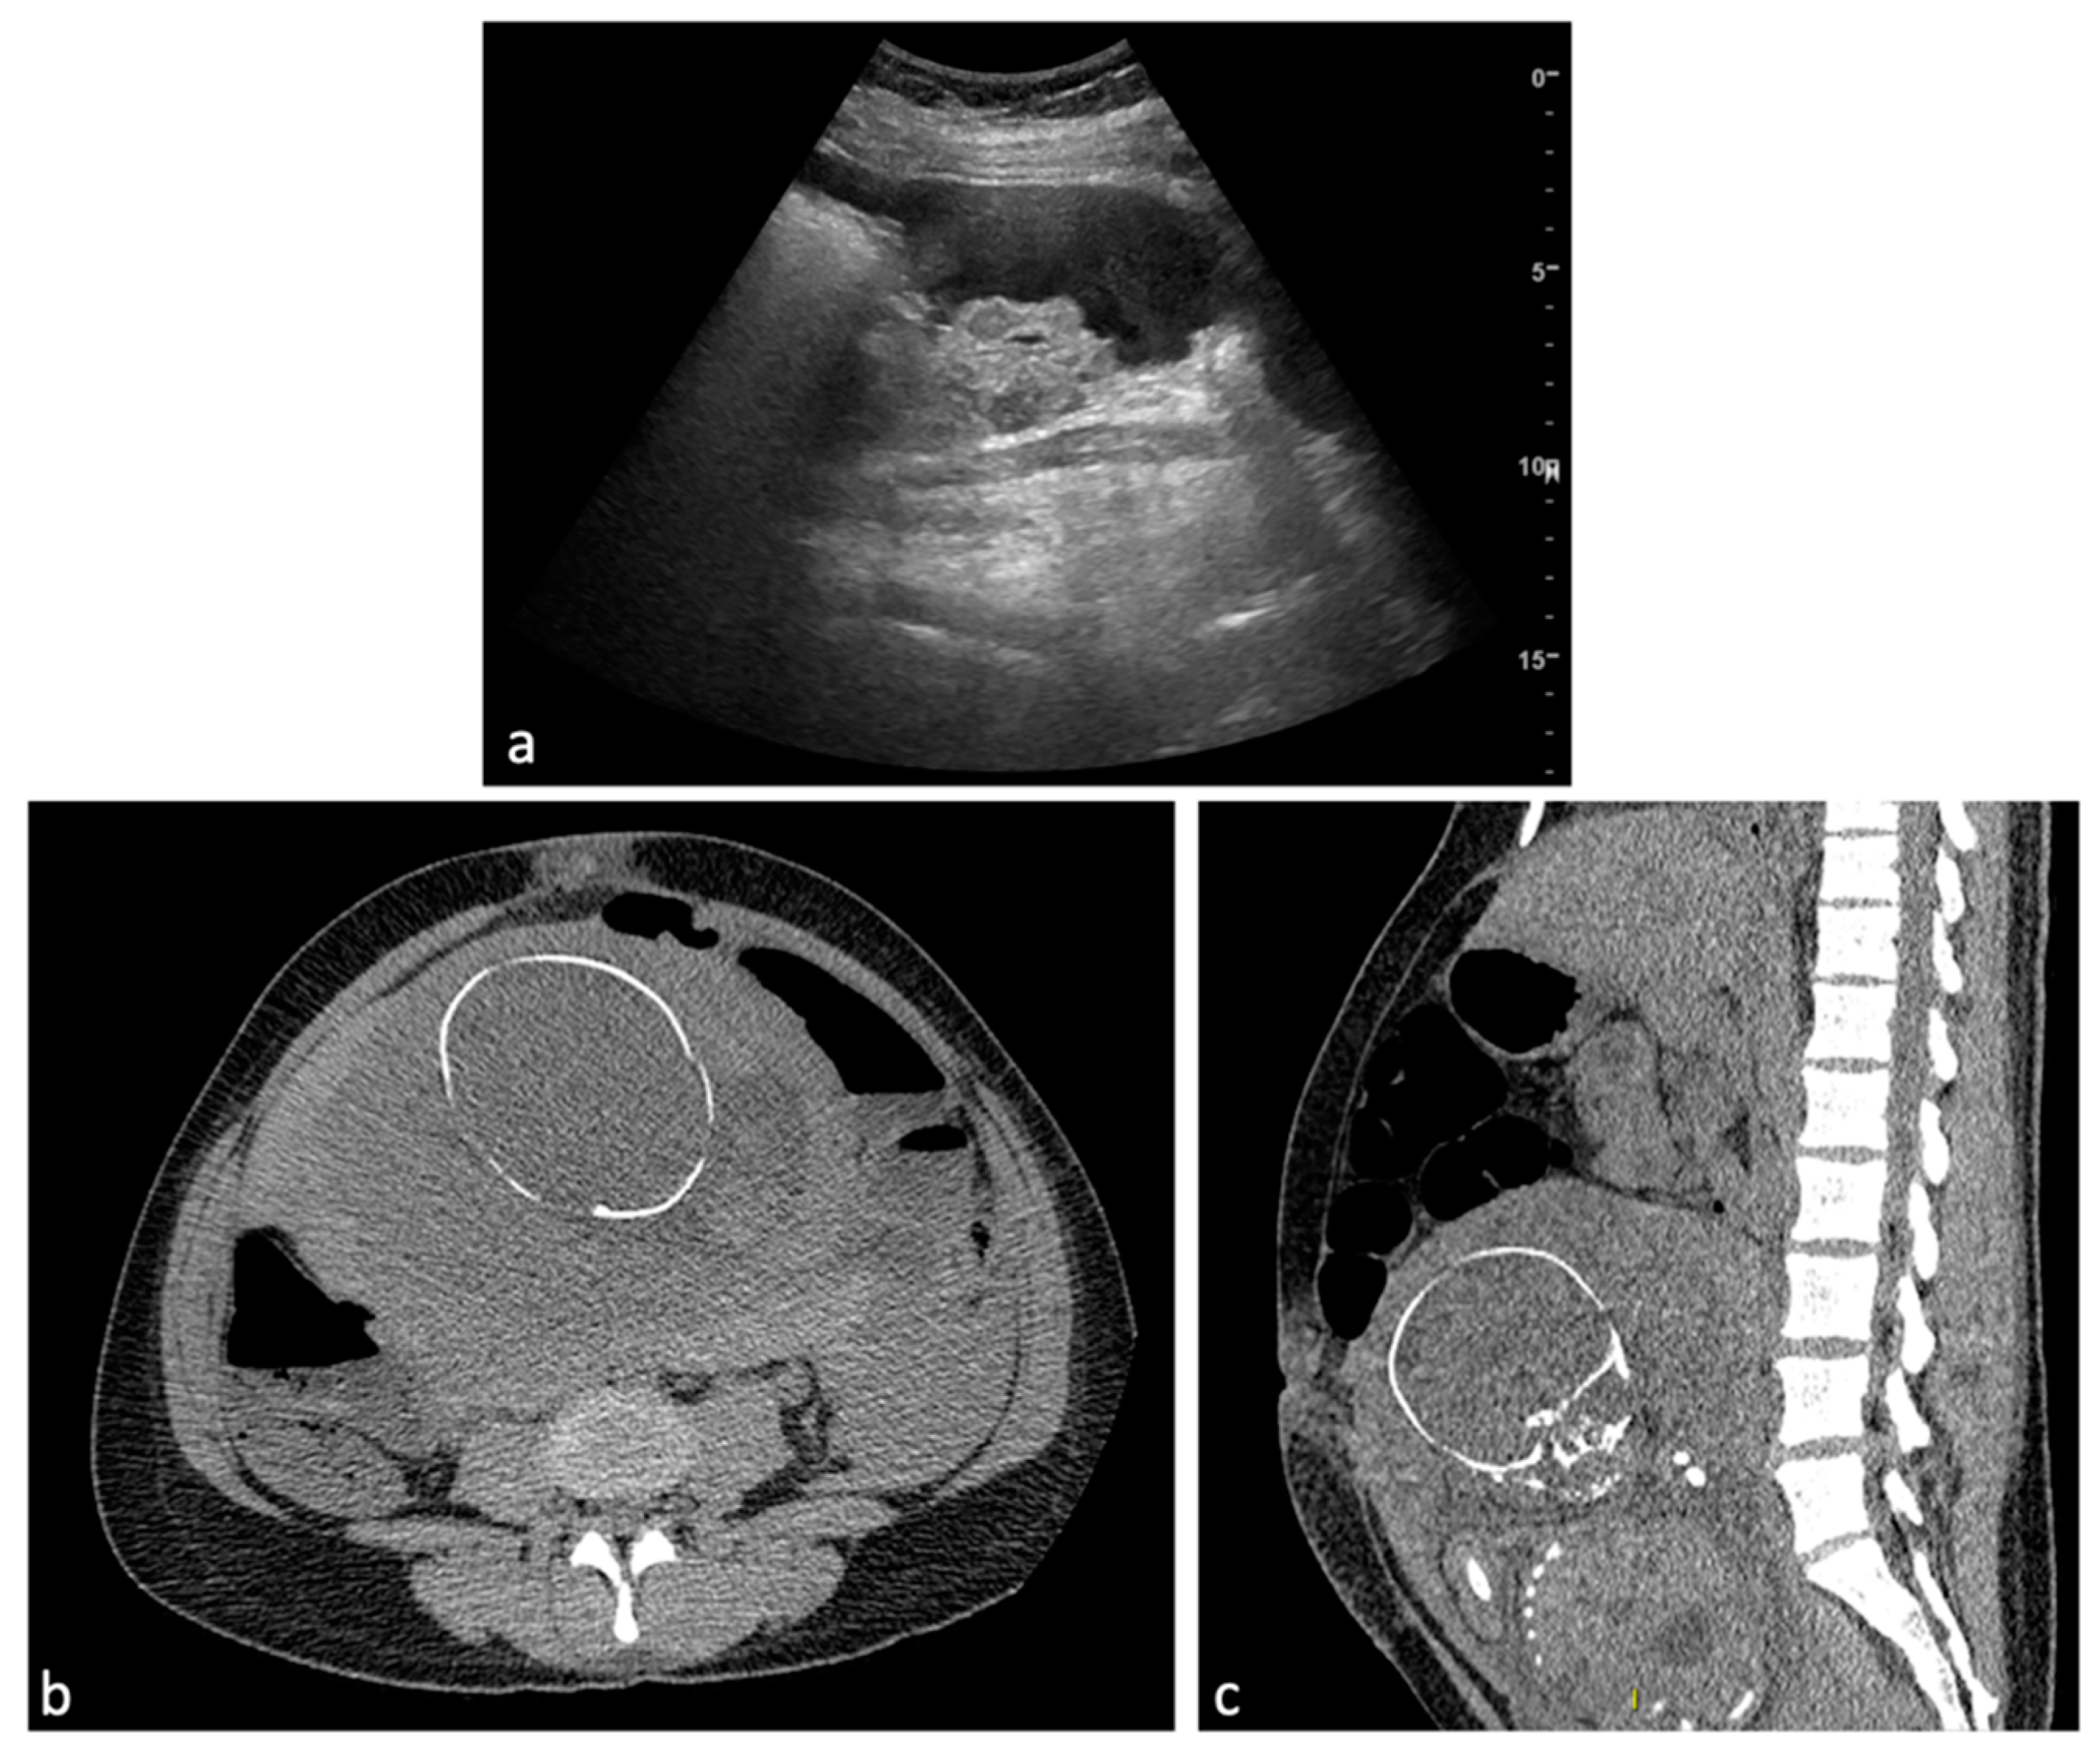

Figure 8.

Uterine rupture. A 39-year-old female patient with a history of laparoscopic myomectomy who was pregnant at 29 weeks presented to the emergency department with abdominal pain and vaginal bleeding. Transabdominal ultrasound demonstrated hemoperitoneum (a) and a live fetus. CT scan without contrast medium (axial, b; sagittal, c) was performed urgently with confirmation of abundant hemoperitoneum. An urgent caesarean section was performed, with evidence of uterine rupture at the posterior wall in the presence of placenta accreta. Hysterectomy was performed.